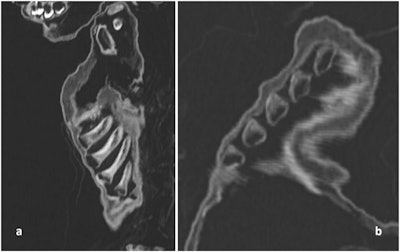

The child's soft tissue showed that he was overweight for his age. But his ribs had a malformation pattern called rachitic rosary, which is often caused by rickets or scurvy.

CT scan of the costochondral junction with an enlargement such as seen in "rickety rosary" but also in "scurvy rosary." (a) Sagittal section; (b) oblique section."The combination of obesity along with a severe vitamin-deficiency can only be explained by a generally 'good' nutritional status along with an almost complete lack of sunlight exposure," Nerlich said in the journal statement. "We have to reconsider the living conditions of high aristocratic infants of previous populations."